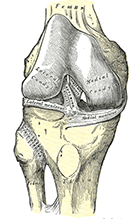

Il ginocchio è la più grande articolazione di carico del corpo umano e presenta una struttura molto complessa costituita, da ossa, cartilagini, capsula e legamenti: ciò rende ragione della difficile biomeccanica di tale distretto e della complessità delle sue patologie.

Le ossa che costituiscono il ginocchio sono i condili femorali, il piatto tibiale e la rotula.

Le cartilagini di rivestimento ricoprono le superfici ossee di contatto. I menischi (mediale e laterale) hanno la doppia funzione di assorbire gli shock e di rendere più congruenti tra loro le superfici articolari.

La stabilità del ginocchio è garantita da una complessa struttura capsulolegamentosa (legamento collaterale mediale e laterale, legamento crociato anteriore e posteriore) e dai muscoli della coscia e della gamba.